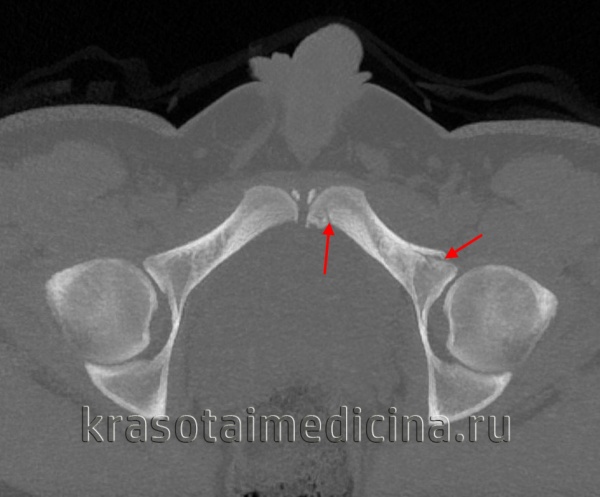

(Слева) КТ у мужчины 19 лет, упавшего с высоты 6 метров и приземлившегося на бок, аксиальный срез. Определяется вколоченный перелом через вторую зону крыла крестца слева, что указывает на травму по типу ла -теральной компрессии. Перелом со смещением правого крестцово-подвздошного сочленения указывает на передне-заднее направление приложения силы по отношению к правой половине таза. Это нестабильный таз, ЛК III.

(Справа) КТ, коронарный срез: у этого же пациента определяется вколоченный перелом крестца слева и полный разрыв крестцово-подвздошного сочленения справа вследствие передне-заднего направления приложения силы. ЛК III встречаются редко. (Слева) При рентгенографии в передне-задней проекции у мужчины 35 лет определяется травма по типу ВТ. Левое крестцово-подвздошное сочленение полностью разорвано, левая половина таза смещена кверху, а также отмечаются переломы лобковой кости справа и подвздошной кости слева. Крестцово-подвздошное сочленение справа расширено спереди.

(Справа) КТ, аксиальный срез: у этот же пациента определяется диффузное расширение левого КПС, указывающее на полный разрыв передних и задних связок левого крестцово-подвздошного сочленения. Правое крестцово-подвздошное сочленение расширено только спереди. (Слева) КТ, 3D реконструкция: у женщины 75 лет определяются переломы по типу ЛК I. Отмечаются косые переломы ветви лобковой кости слева и вколоченный перелом 2 зоны крестца слева.